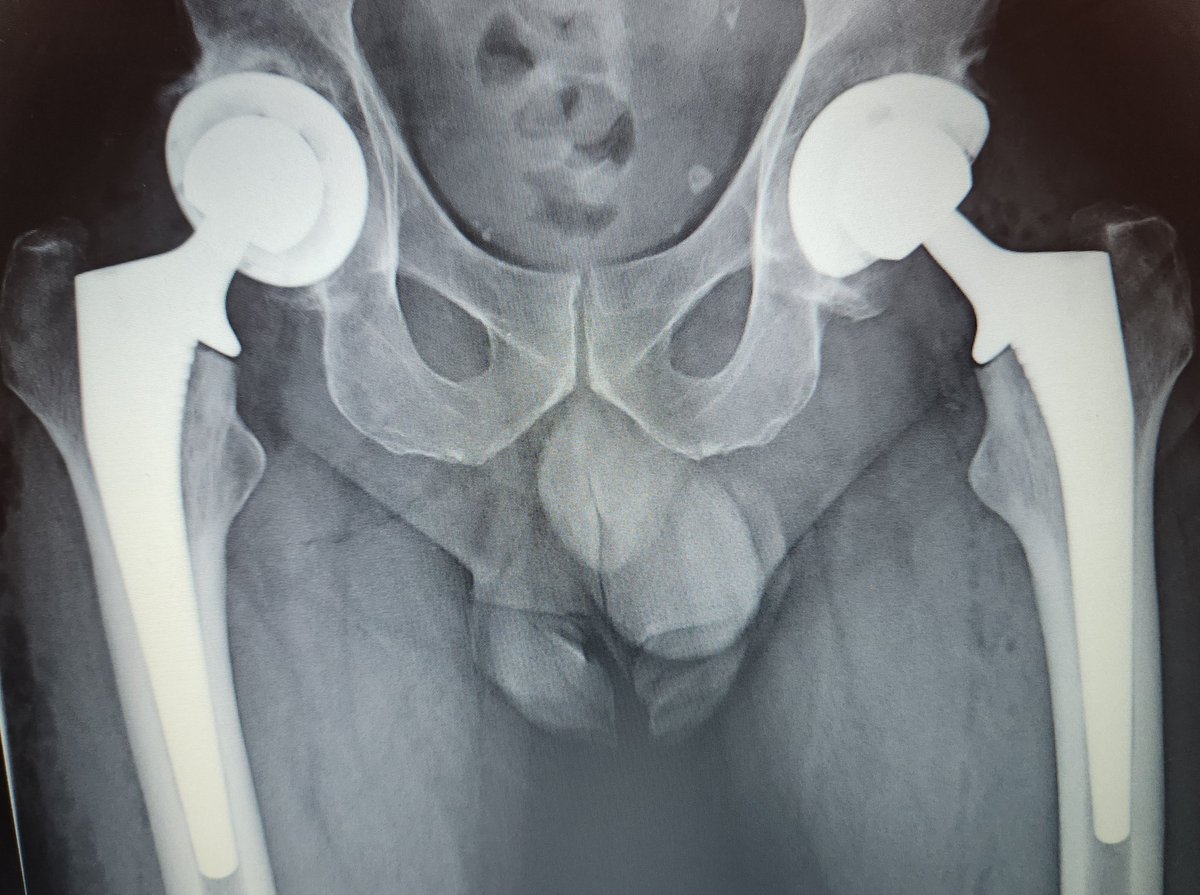

These are expensive too and a lot of hard work goes into getting pt on table. Thank you to YGC theatres & staff for the effort, @BetsiCadwaladr for support, fantastic MDT Wrightington, North Wales MDT, surgical experience @CavendishHip, my colleagues & Mr Kapur for dual operating